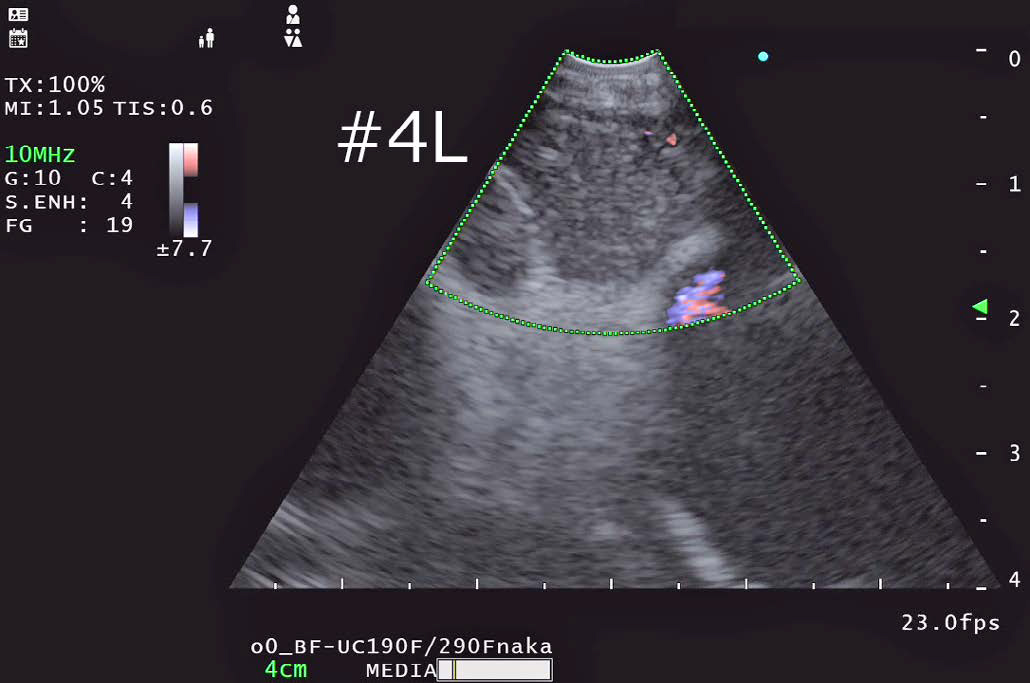

• 4L リンパ節穿刺

FLOW モード

•  EU-ME2と同様に右記のドプラーモードが使用可能である。

基本となるBモードの解像度が向上している影響か、色のにじみが少なくメリハリの利いたドップラー画像になっていると感じた。

当院ではTBNA施行時には血管からのはみ出しを抑えて血流表示するハイフローを基本的に使用し、穿刺前に血管介在を確認している。

• パワーフロー:血流の強度をカラー表示